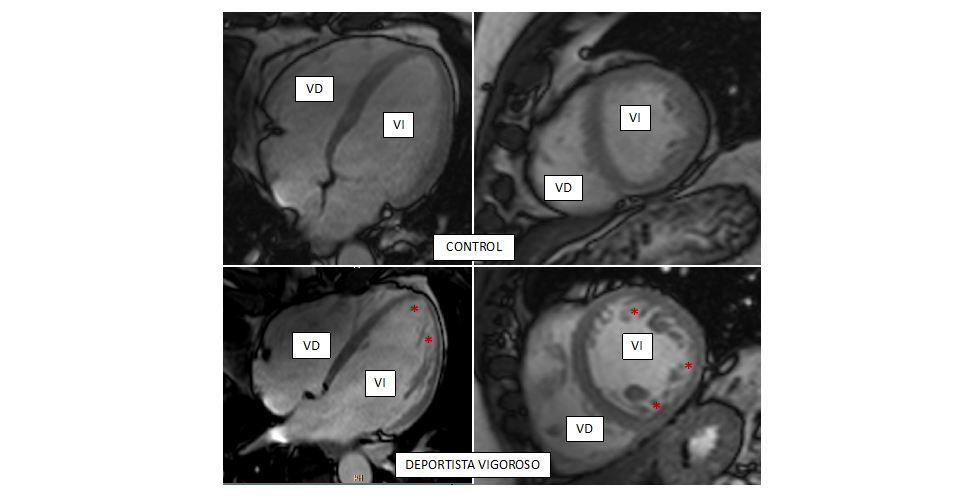

• CIBERCV

Identificado el papel de la proteína CCT en el control de la formación de la sinapsis inmune

09/12/2020

Identifican una nueva diana diagnóstica y terapéutica para la enfermedad cardiovascular

03/12/2020